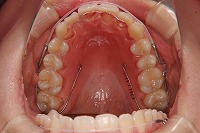

反対咬合を主訴に来院された、右側唇顎裂の10歳6ヵ月の女の子です。診断「右側唇顎口蓋裂で反対咬合を伴う」1期治療で反対咬合の解消と上顎の前歯の並びを修正しました。2期治療は抜歯をせず治療を行いました。